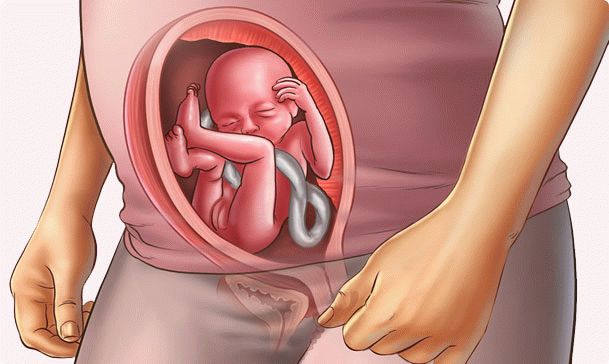

Le développement du fœtus

En toi, un vrai homme grandit. Il a des proportions presque similaires à celles d'un nouveau-né. La croissance est de 14 à 16 cm et le poids est d'environ 260 g. Le fœtus passe presque toute la journée au repos et ne bouge que quelques heures par jour. Le petit cerveau envoie des signaux et votre bébé "essaie les forces":

- déplace les bras et les jambes;

- tourne avec tout le corps;

- bouge la tête;

- ouvre et ferme une bouche;

- suce les doigts (habituellement "tombe sur" gros);

- attrape parfois le cordon ombilical;

- gonfle légèrement la poitrine, comme pour respirer.

Le petit cœur pompe le sang de manière stable. Une petite quantité de liquide pénètre constamment dans l'estomac du bébé. Il est transformé en urine et excrété dans la vessie fœtale. Le liquide amniotique est régulièrement mis à jour, de sorte que le bébé ne se trouve pas dans un environnement toxique.

Mais les intestins ne fonctionnent pas encore à pleine puissance. Les particules qui y restent sont collectées dans le méconium, les excréments d'origine. Il sera élevé à la naissance du bébé.

Un autre processus important. La peau mince du bébé commence à se diviser en couches.